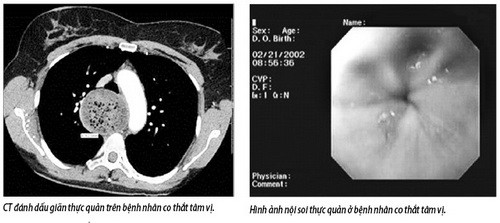

Bệnh co thắt tâm vị có đặc điểm nổi bật là rối loạn hoạt động của thực quản. Đoạn cuối của thực quản đổ vào dạ dày bị co thắt và hẹp lại, còn đoạn trên bị giãn to ra. Bệnh nhân có thể bị tử vong đột ngột do phản xạ tim mạch hay dây thần kinh X, do ngạt thở vì trào ngược thức ăn vào khí quản, do suy dinh dưỡng ở giai đoạn muộn.

Bệnh tiến triển tiềm tàng, khi bệnh nhân đến khám thì thực quản thường đã giãn to. Lâm sàng thường có các biểu hiện khó nuốt, nuốt nghẹn. Vấn đề đó thường xảy ra đột ngột, có người sau xúc động mạnh. Thức ăn nuốt vào bị ứ lại đột ngột, nhất là thức ăn đặc.